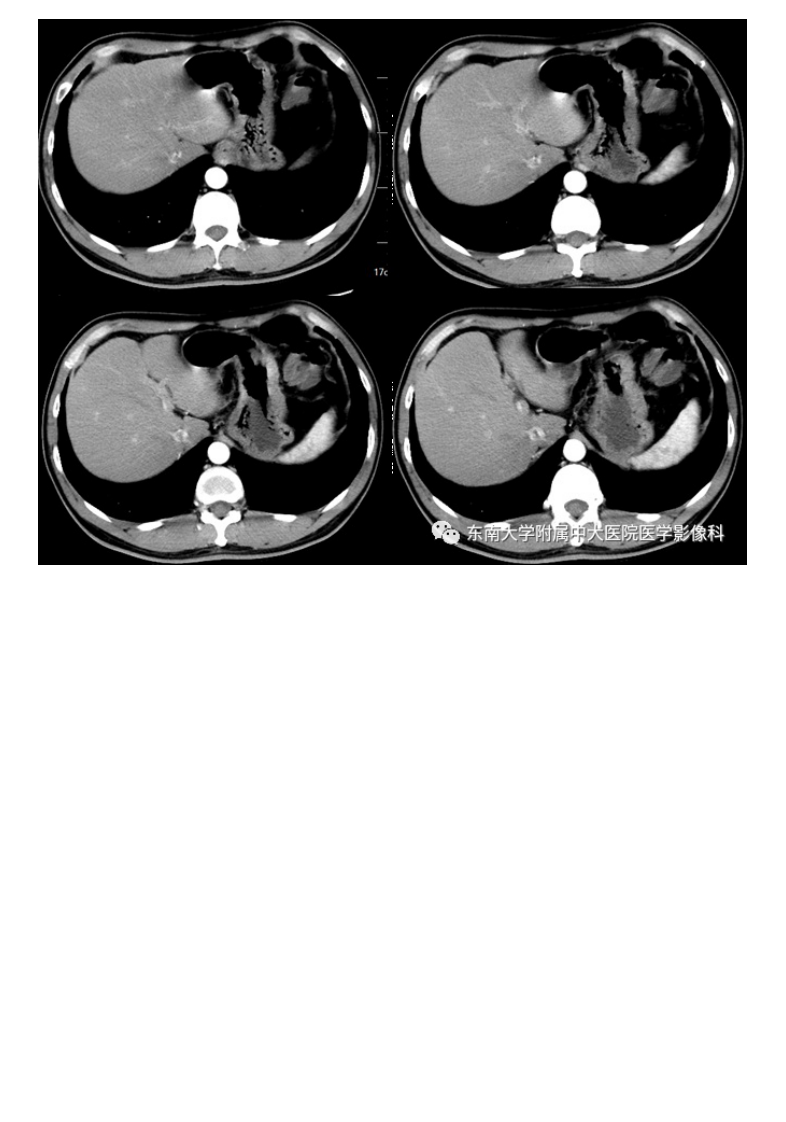

20210113_2【晨读结果公布】2021.01.13消化系统疾病——胃内异位胰腺.pdf